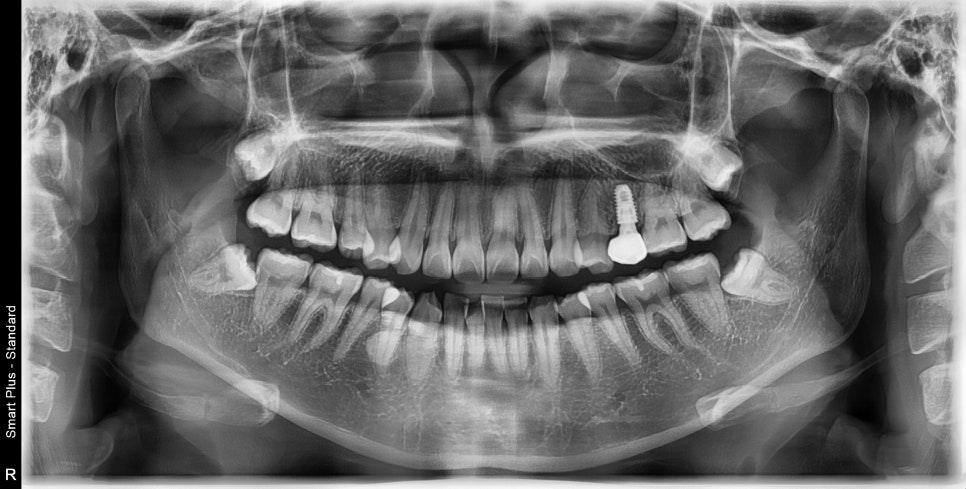

인플란트가 하나 있는 환자분이 교정치료를 하고 싶어 내원했습니다.

화살표 치아가 임플란트 였습니다.

처음 교정을 하러 오셨을때는 기존의 임플란트 머리 모양을 '갈아서=삭제해서' 변형시킨 뒤 교정치료를 진행했고,

나사를 모두 교체하거나, 제거하는 방법은 환자분이 너무 힘들어서 '나사'는 유지할 수 있으면 유지하고 있습니다.